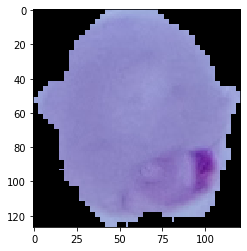

含有疟疾细胞的样本图像

缩影图像: